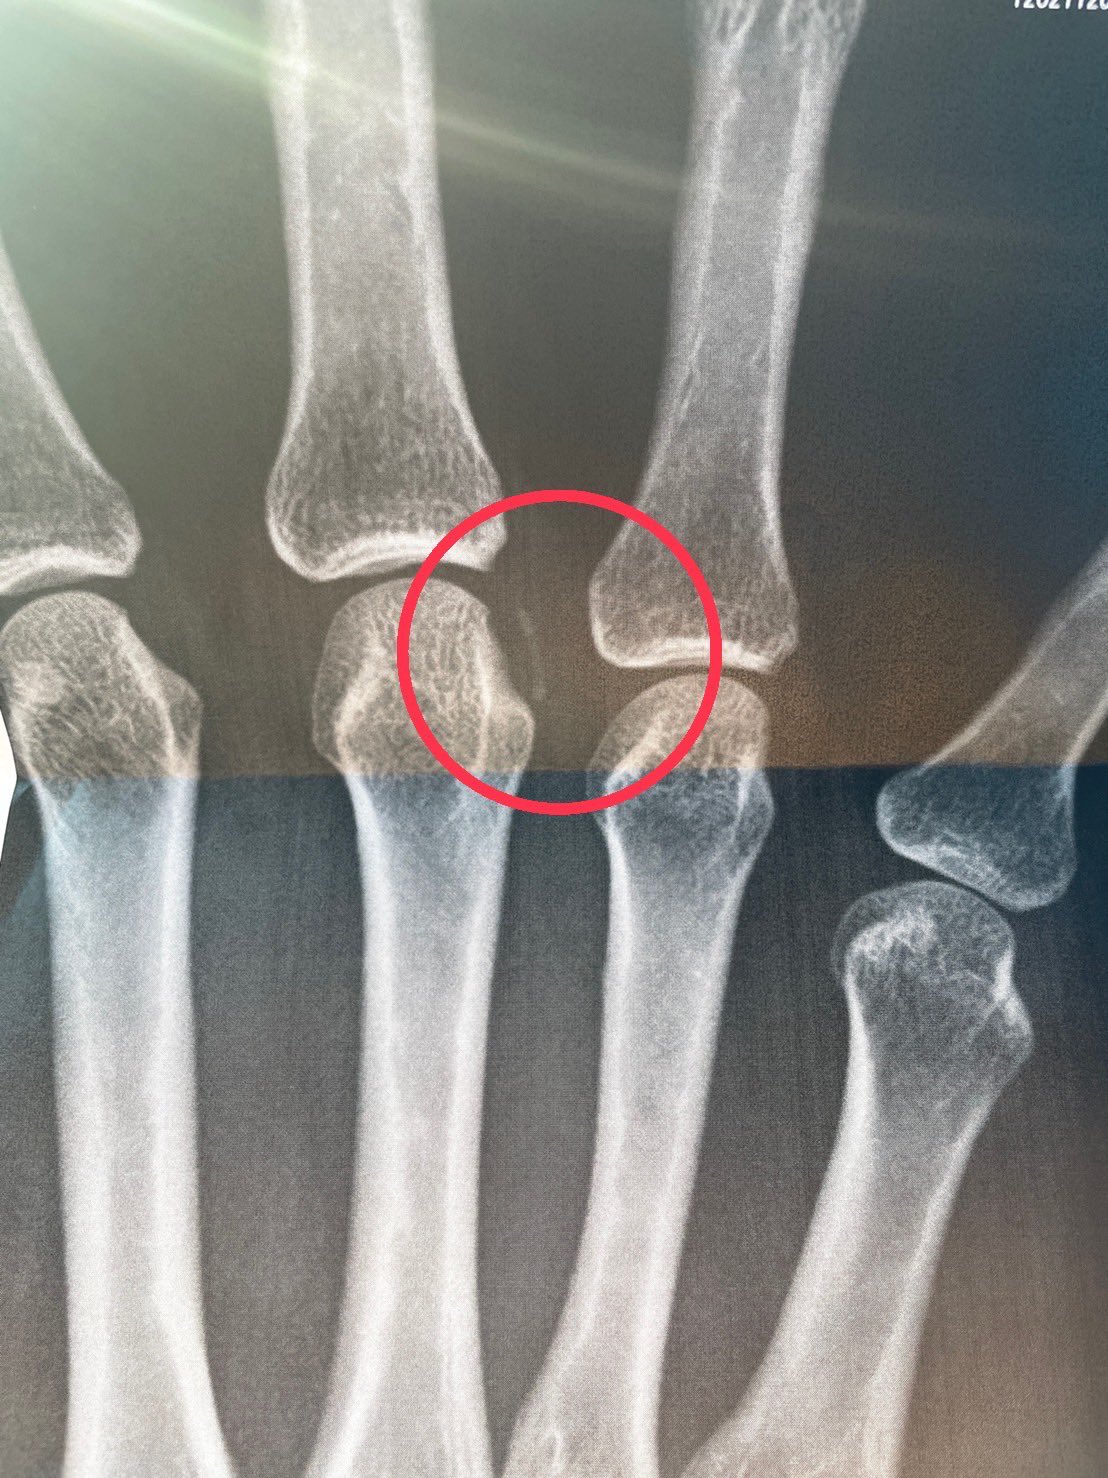

突き指と剥離骨折の違い 今回の娘の症状ですが、腫れはひどくなく内出血はしていますが握れます。 握れる時点で骨折はしていないと素人判断をしましたが、大きな大会前ですのでとりあえず接骨院に行きました。 レントゲンで剥離骨折だとわかりまし 剥離骨折はポキッと折れる骨折と違い、骨折していることに気がつかないことも多いようですので、親がしっかり判断してあげることが大切です。 手の指を剥離骨折した長女の経緯と完治までについてまとめました。 目次 剥離骨折とは? 剥離骨折した

剥離骨折 指 レントゲン

指骨骨折 の治療には、保存療法と手術療法があります。 骨のずれがない、または軽度の場合は添え木やテーピングを使用した保存療法を行うことが多いです。 保存療法では、固定後も何度か定期的に整形外科を受診し、レントゲンによる骨の治癒過程の 剥離骨折の場合 保存療法では指の 第一関節を過伸展 とし、その状態で剥離した骨片(骨のかけら)を指で押して整復します。 指を反ったまま専用装具やマレットフィンガー用に形作ったアルフェンスシーネで過伸展を保ち3~4週間ほど固定します。 剥離骨折が疑われる場合には、詳細に評価するために、画像検査を行います。 レントゲン検査 骨のずれや骨折の有無などを詳細に評価して診断します。 ct・mri検査 レントゲン検査で診断がつかない場合には、ctやmriなどの画像検査を行うこともあります。